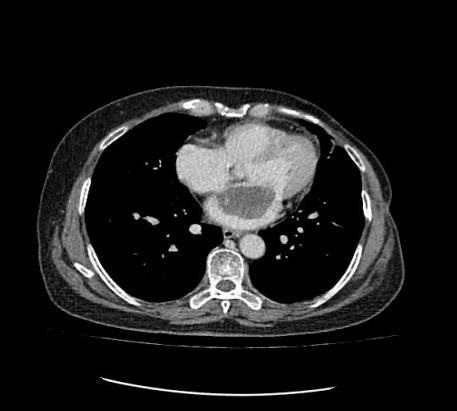

通訊員許欣報道:近日,我院心胸外科、麻醉科、手術(shù)室通力合作,為一名身患左房粘液瘤患者成功實施了胸腔鏡輔助下微創(chuàng)左房粘液瘤切除術(shù)。

患者為一57歲的女性,心慌、胸悶的癥狀已有年多,一直以為是“感冒”而沒放在心上。最近經(jīng)人介紹到我院檢查,經(jīng)心臟超聲檢查發(fā)現(xiàn)左心房上長了一個雞蛋大小的黏液瘤。雖說是良性的,但生長位置在二尖瓣口,如果黏液瘤碎片或瘤體表面血栓脫落,可發(fā)生體循環(huán)或肺循環(huán)的栓塞,隨時有猝死的危險。以往此類疾病必須通過傳統(tǒng)胸部正中切口實施手術(shù),病人術(shù)后要經(jīng)過3-6個月左右的恢復(fù)期,患者創(chuàng)傷大、恢復(fù)慢、出血較多、切口瘢痕明顯、心理負(fù)擔(dān)重,無論是對身體還是心理都是一次嚴(yán)重創(chuàng)傷。為患者實施全胸腔鏡技術(shù)摘除左心房黏液瘤手術(shù),在不破壞患者破壞胸骨穩(wěn)定性的前提下,只需在患者胸壁上開2個“鑰匙孔”樣大小觀察孔和1個4cm的操作孔即可進(jìn)行手術(shù),最大限度減少術(shù)后疼痛和創(chuàng)傷,縮短術(shù)后恢復(fù)時間。